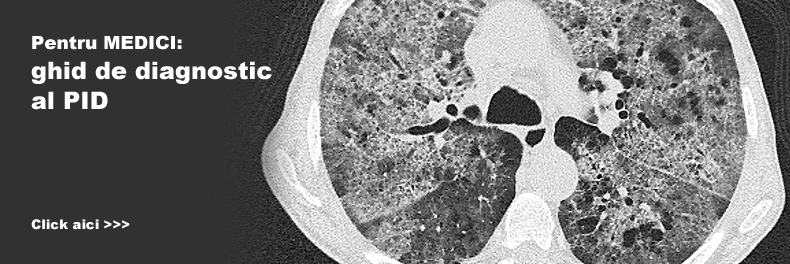

PID pentru medici

Ghid de diagnostic al PID